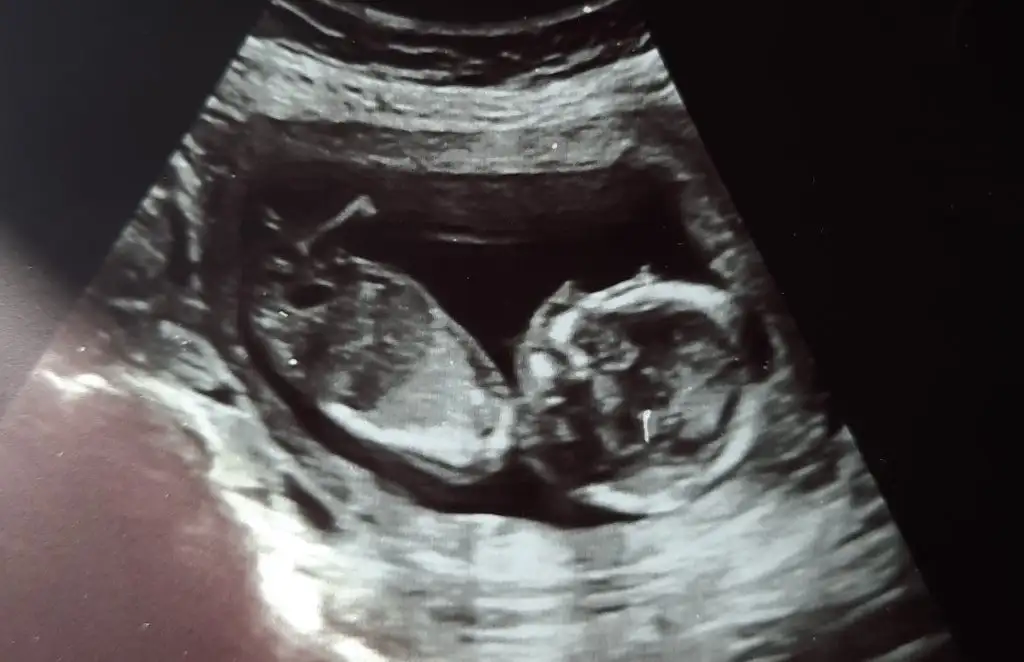

Selam kızlar ben geldim kontrolden 2 li düşük risk çıkmış çok şükür. Doktora rica ettim ama cinsiyeti malesef yine söylemedi devlet de .. fotoğraf da nub görünüyor sanki yanlış görmüyorsam bence kız, sizce ???